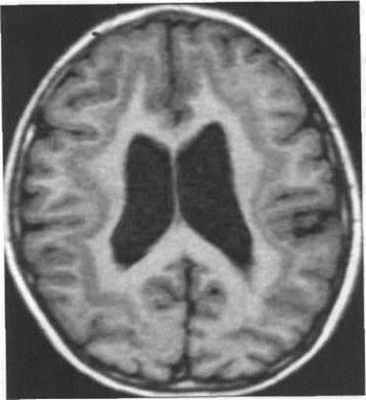

Классическая (тип I) лиссэнцефалия.

Т1-взвешенная аксиальная МРТ: (мутация LIS I) толстая корковая лента с гладкой поверхностью и прямой, неволнистой границей между серым и белым веществом.

Обратите внимание на присутствие нескольких мелких борозд в лобной области и полное отсутствие борозд сзади,

отсутствие оперкуляции с широко открытой сильвиевой бороздой и слоистость коры со слабой границей между гетеротопированными и полностью мигрировавшими нейронами.